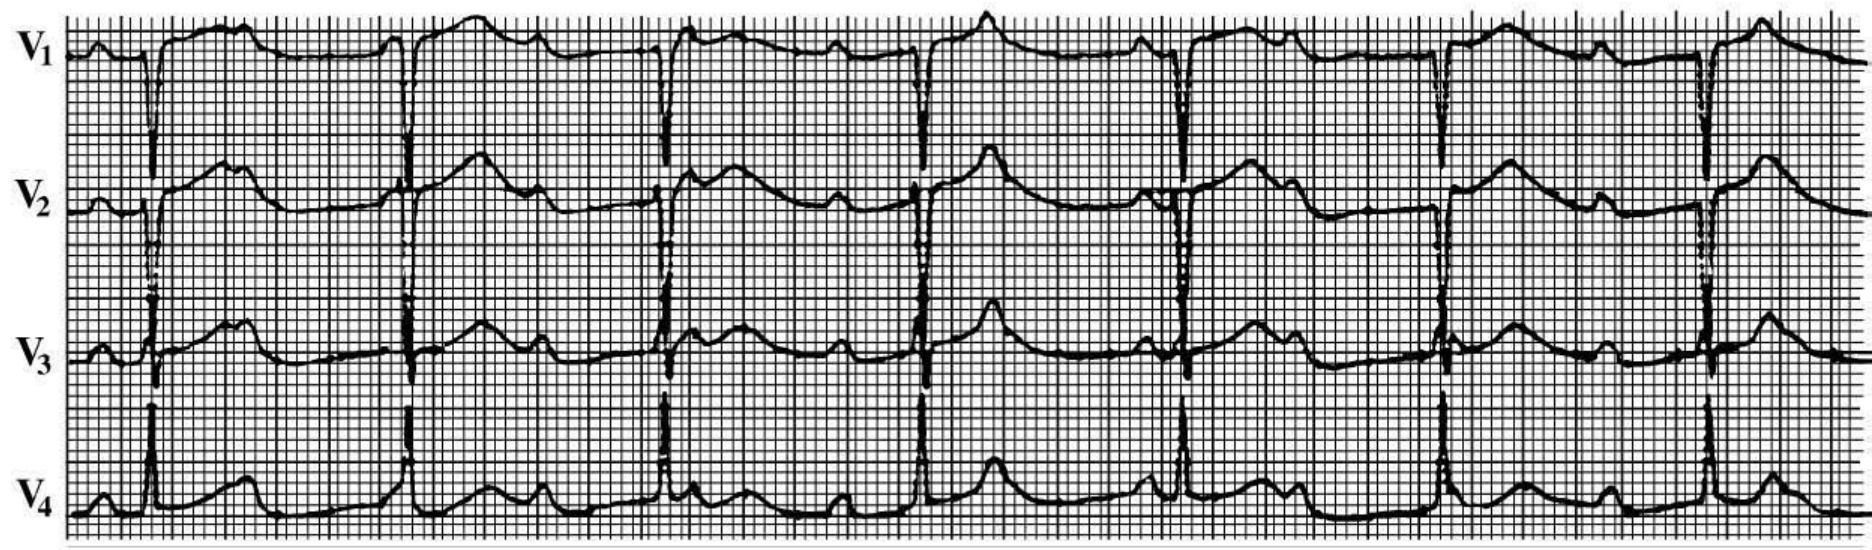

图13-1 病毒心肌炎心电图

患者男性,22岁,病毒性心肌炎。心电图示,P-R间期0.40s,TU融合